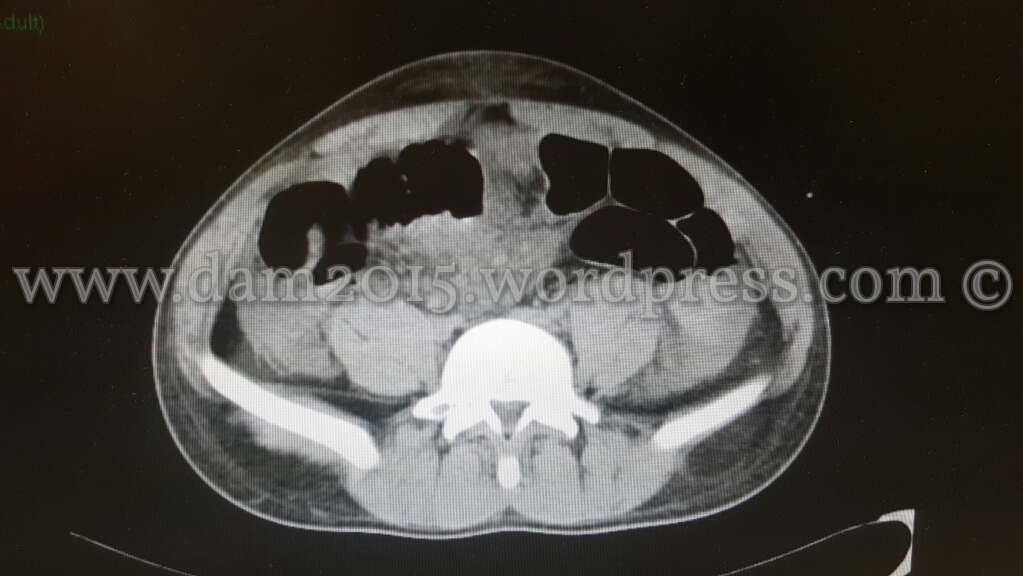

Paziente uomo, 20 anni, caduta accidentale con la bicicletta.

Trauma contusivo diretto dell’impugnatura del manubrio in regione mesogastrica.

Eseguita TC addome che mostrava imbibizione emorragica del tessuto adiposo sottocutaneo della parete addominale in sede mesogastrica e del tessuto adiposo omentale contiguo, peraltro lievemente erniato attraverso la cicatrice ombelicale.